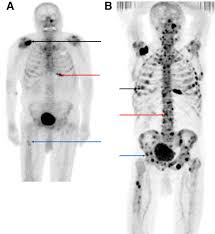

Psa was only 62 to begin with. The link between prostate cancer and osteoporosis. A tiny amount of radioactive substance will be injected into a vein. Imaging studies show skeletal mass and metastasis throughout the body, including the prostate bed. A bone scan is an imaging test that helps to detect bone diseases and injuries. Bony metastases from prostate cancer shown by a bone scan. A radioactive material called a radiotracer is injected into the patient's bloodstream and accumulates predominantly in the bones where it can be detected by a gamma camera. Because these scans are limited in their ability to track treatment responses, researchers have been searching for ways to standardize bone scan measurements.

In relation to mri scans, bone scans tend to be cheaper. A bone scan does not need any special preparation. for @aural, most all men diagnosed with a g8 are referred for a ct scan and bone scan; There are a few types of biopsy that may be used in hospital, including the below. However, a ct scan also shows bones and can be used to track whether the prostate cancer has spread to any nearby areas or begun to grow on any of the surrounding organs. Anterior and posterior bone scans of a patient with prostate cancer, with metastasis to the 12th rib and thoracic spine represented by the increased uptake of isotope. prostate cancer can sometimes spread from the prostate to the bones, which is known as bone metastasis. The link between prostate cancer and osteoporosis.